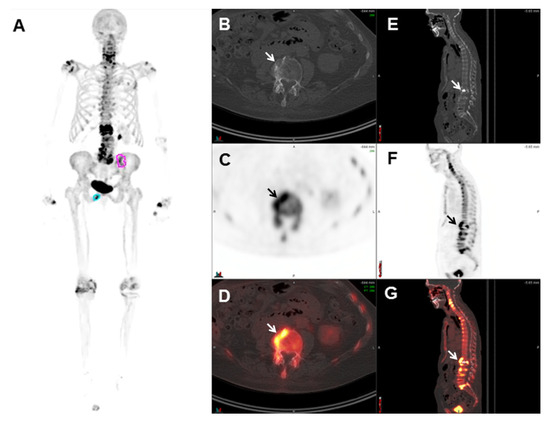

2.5.1. 68Ga-PSMA-11

- Rauscher, I.; Maurer, T.; Fendler, W.P.; Sommer, W.H.; Schwaiger, M.; Eiber, M. 68Ga-PSMA ligand PET/CT in patients with prostate cancer: How we review and report. Cancer Imaging 2016, 16, 14. [Google Scholar] [CrossRef]

- Hofman, M.S.; Hicks, R.J.; Maurer, T.; Eiber, M. Prostate-specific Membrane Antigen PET: Clinical Utility in Prostate Cancer, Normal Patterns, Pearls, and Pitfalls. Radiographics 2018, 38, 200–217. [Google Scholar] [CrossRef]